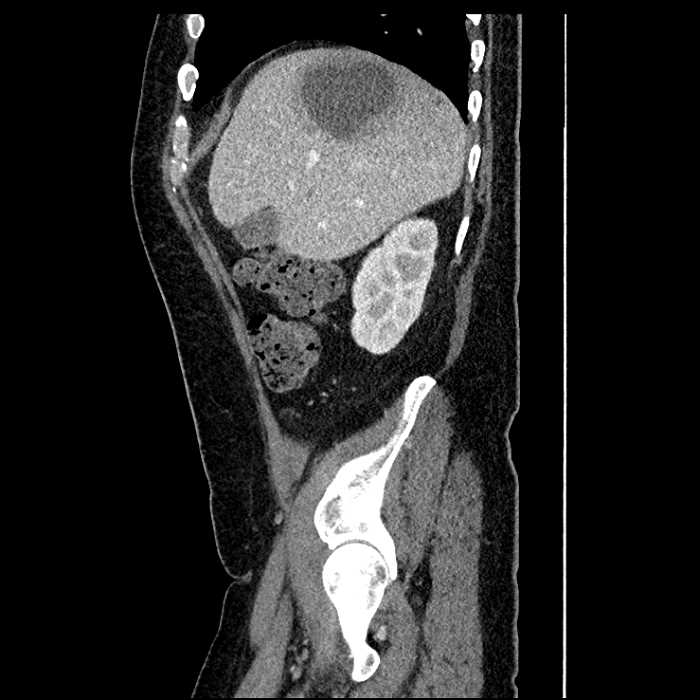

• Large fluid density structure in hepatic segments 7 and 8 measuring 10 x 7 x 7 cm with internal septation and circumferential ill-defined low density compatible with edema

• Peripherally enhancing subcapsular collections along the anterior margin of the left hepatic lobe measuring 3 x 1 cm and 2 x 1 cm

• Clearly marginated fluid density structure in segment 7 and several other scattered tiny hypodensities, which likely represent cysts

Acute sigmoid diverticulitis complicated by a small contained perforation and a large abscess in the right hepatic lobe. Additional small subcapsular abscesses along the anterior margin of the left hepatic lobe.

• The classic CT imaging appearance is a double target sign with internal low density surrounded by an internal enhancing rim (capsule) and a low density external rim (edema)

Hepatic abscess showing the double target sign with low density internally surrounded by a thin inner enhancing rim (red arrow) and ill-defined outer low density rim (yellow arrow). Blue arrow indicates an internal septation. Red arrows: additional smaller subcapsular abscesses. Red arrow: focal contained perforation associated with diverticulitis.